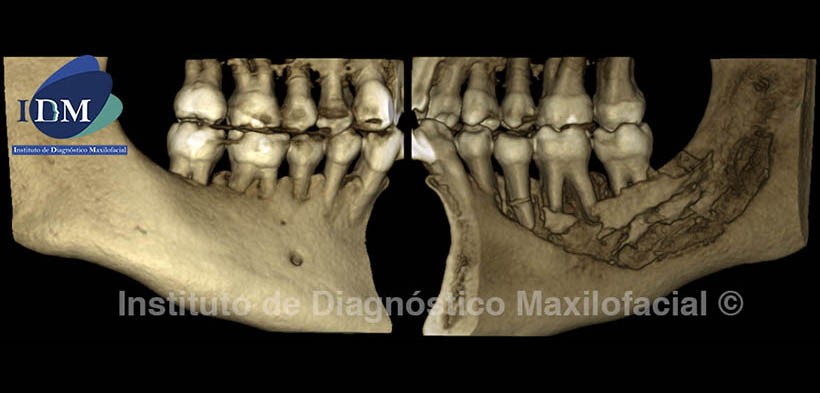

La reconstrucción 3D (Fig. 6) nos muestra el grado de destrucción ósea de la tabla osea lingual, así como los secuestros óseos resultantes del proceso infeccioso.